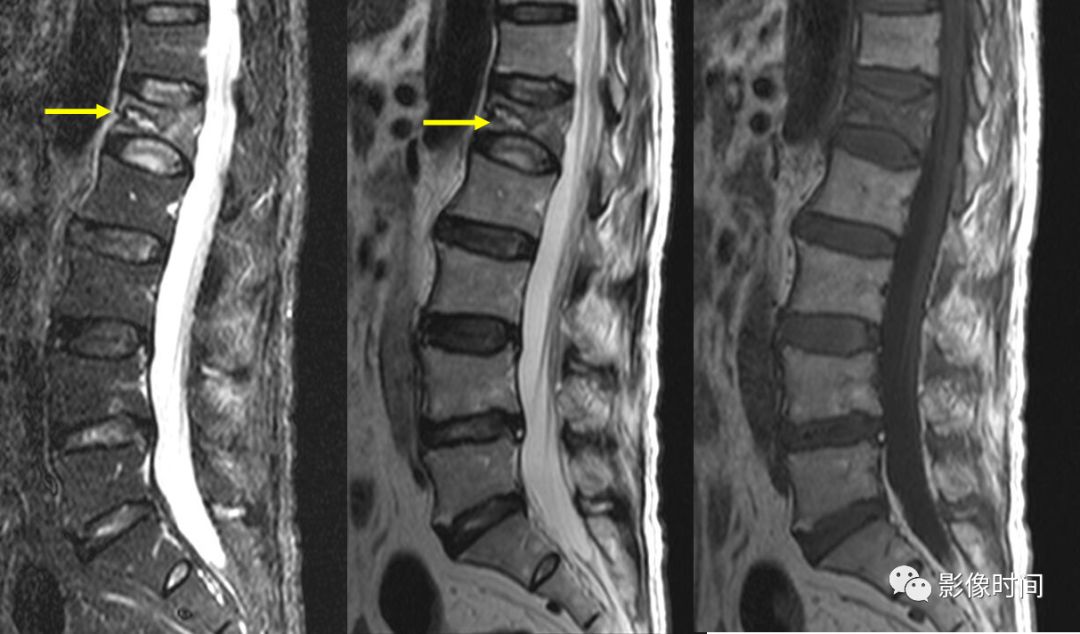

9

MR 液体征

MR 液体征为椎体压缩骨折 MRI 征象,表现为液体敏感序列中在塌陷椎体水肿背景上出现局灶性、线样或三角形更高信号(黄箭),信号强度与脑脊液相仿,T2WI 亦可显示(黄箭)。常提示良性压缩性骨折。

典型病例

67 岁男性,骨质疏松压缩性骨折。MRI 的 T2WI 及脂肪抑制像示两个压缩椎体内可见高信号,与脑脊液相仿(红箭示)。